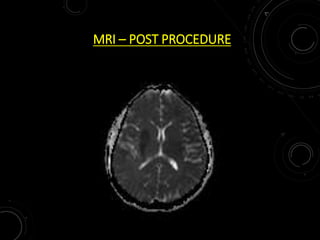

MRI – POST PROCEDURE

MRI – POSTPROCEDURE